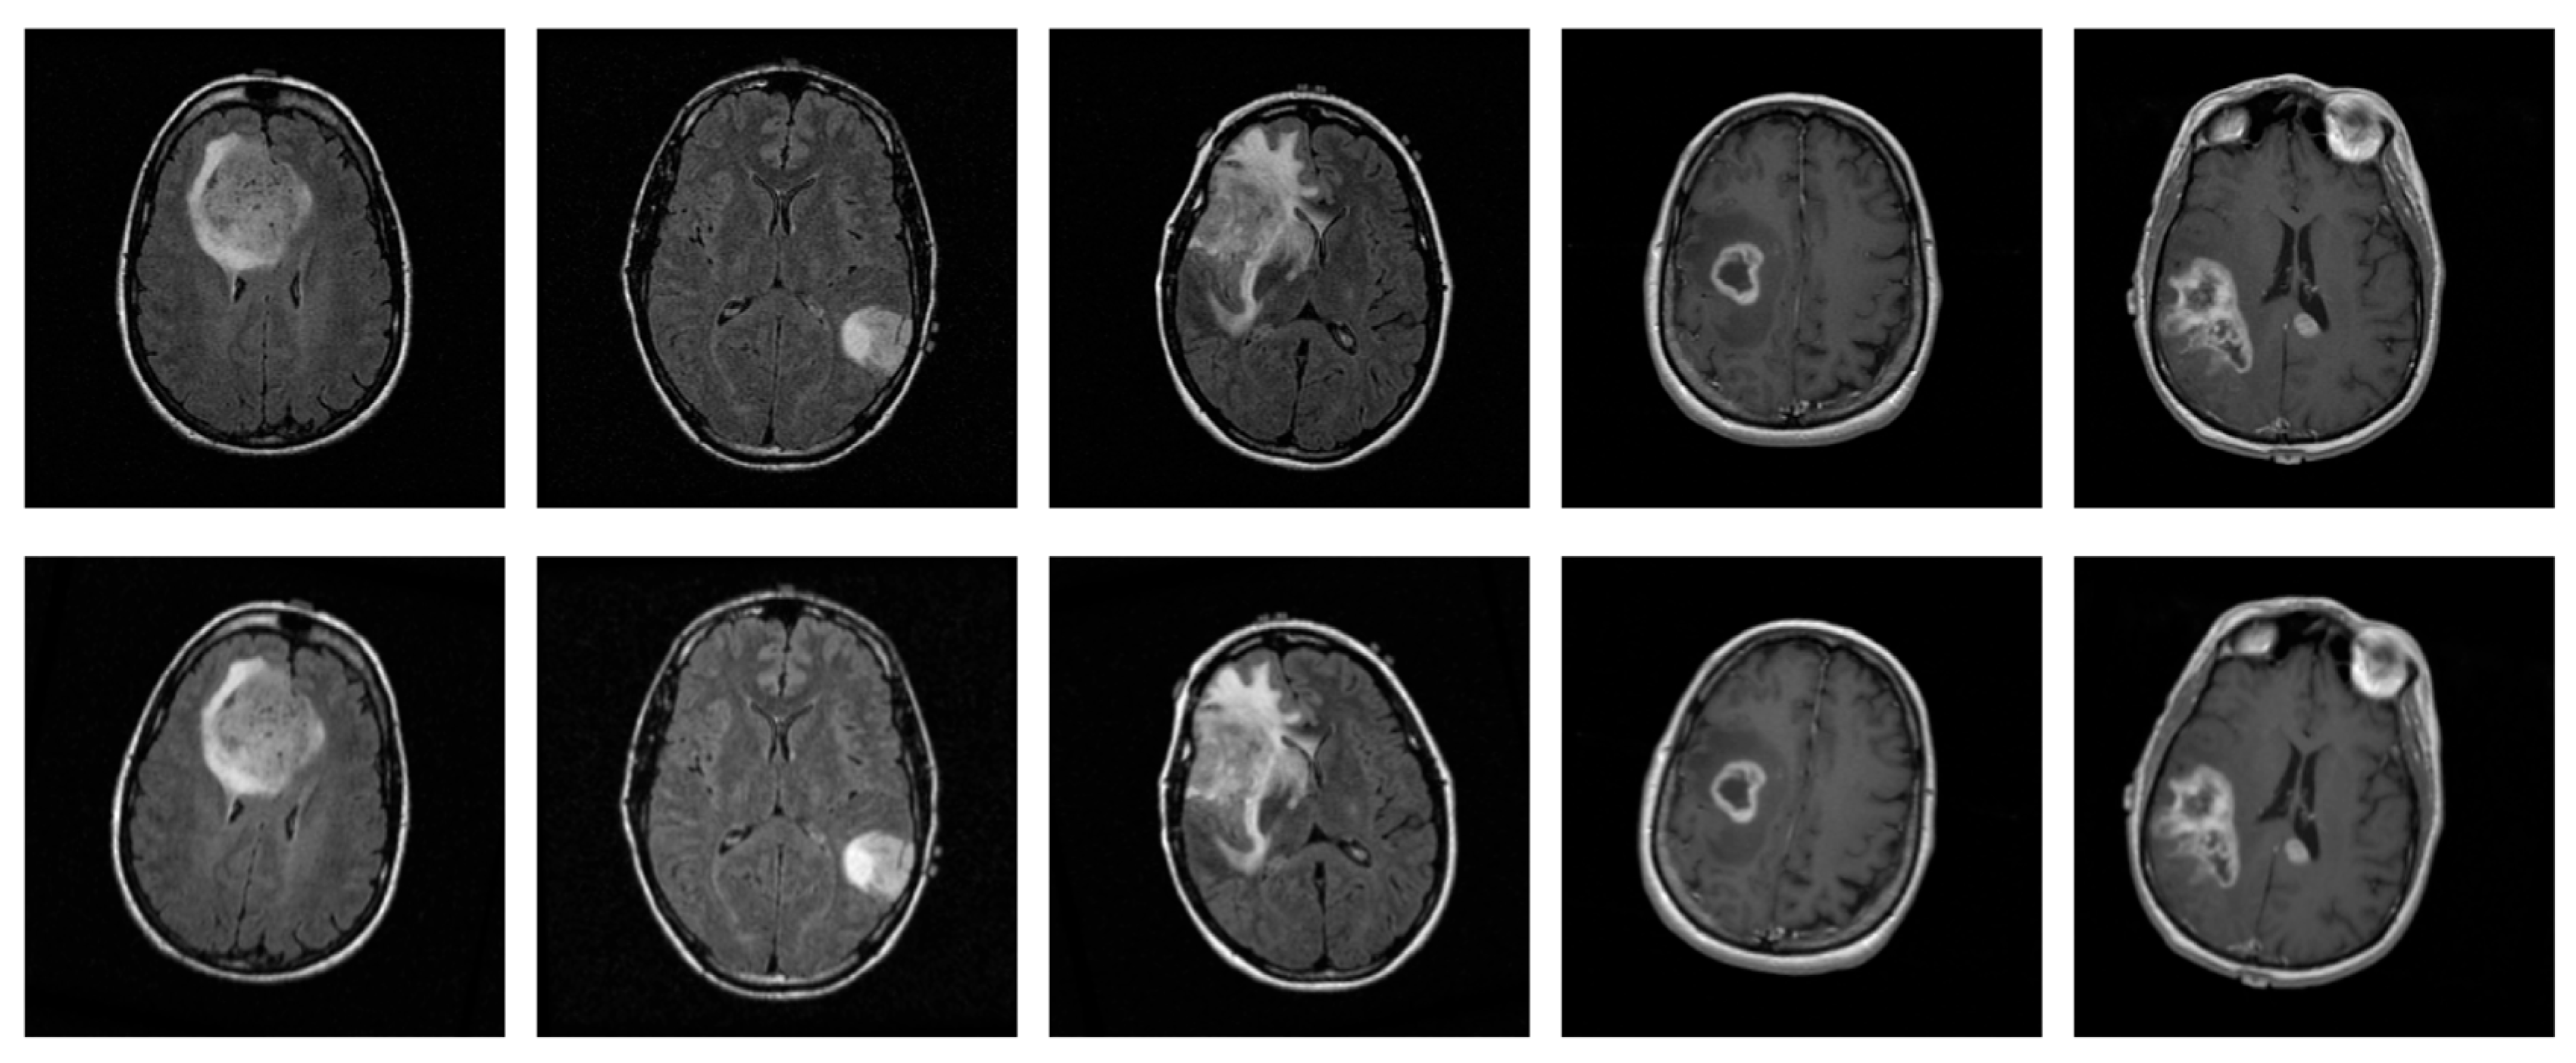

2.1. Data Collection

2.2. Data Pre-Processing

3.3. Effect of Augmentations on the Performance of the Proposed CNN